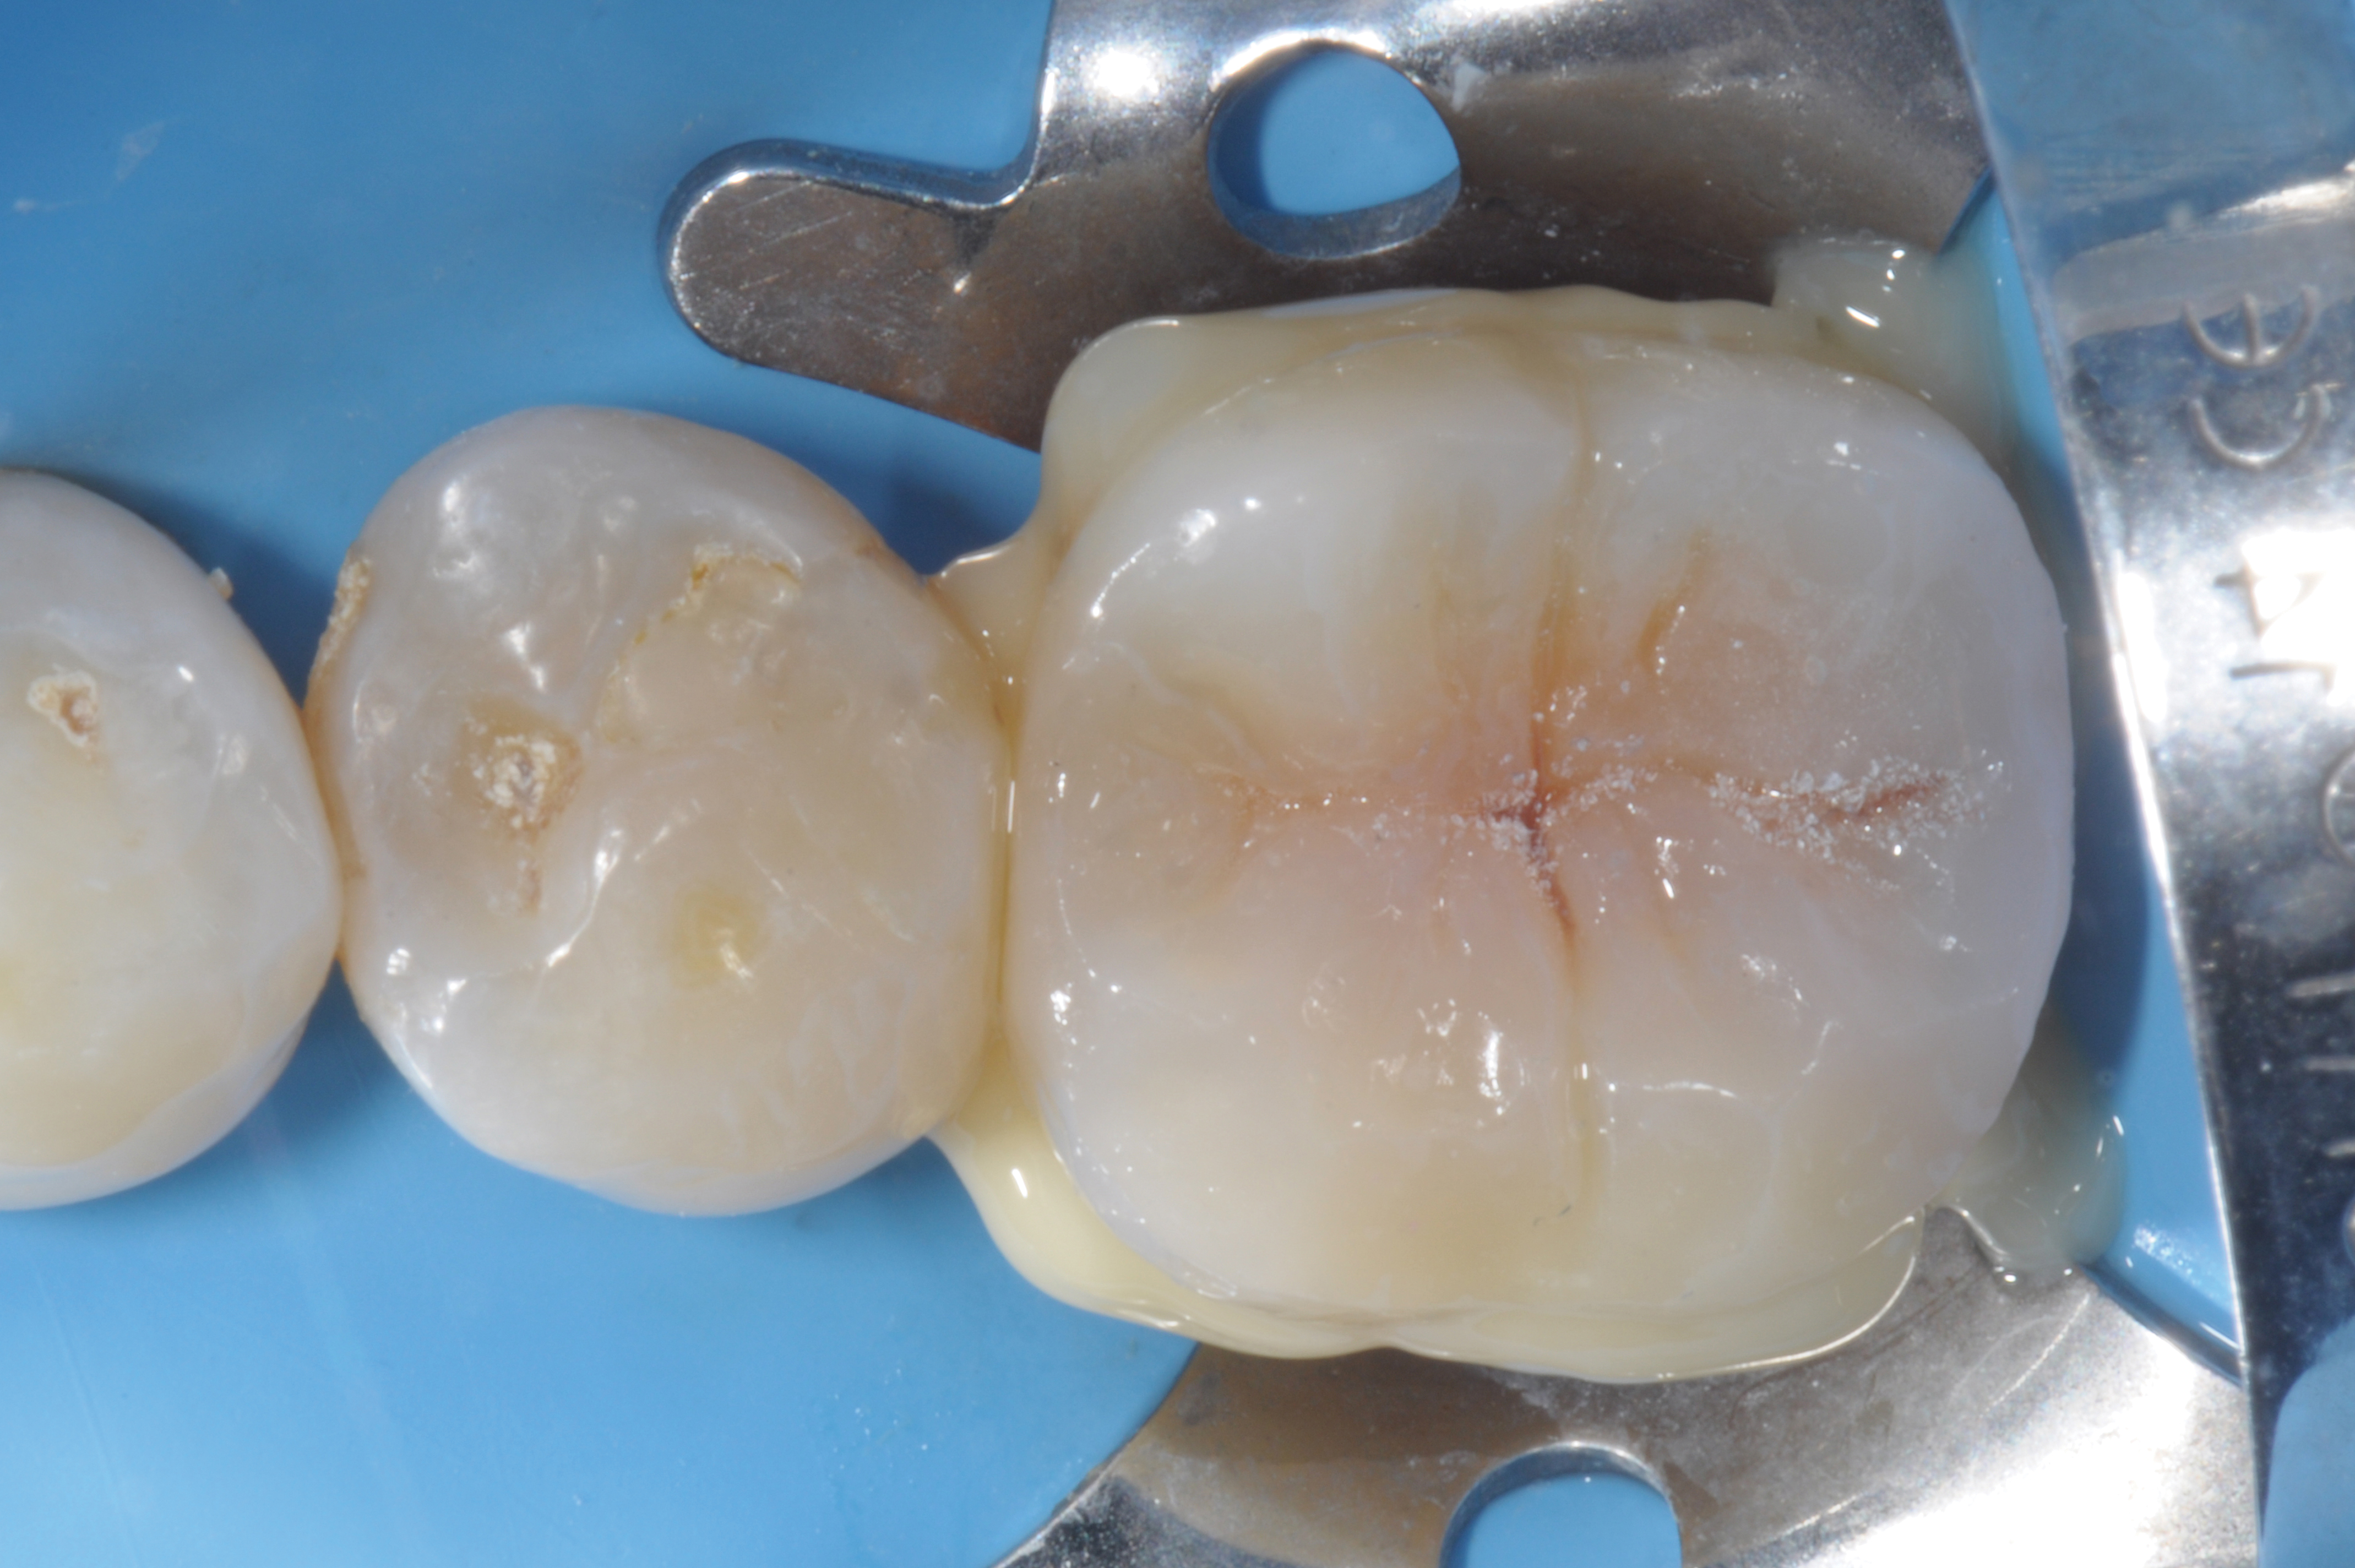

When following a protocol of cementation using an adhesive system, constant rubber dam isolation and careful hand finishing are necessary to provide predictable clinical results (Figure 1 through Figure 4).2

Fig 2. Immediate dentin sealing.

Figure 2

Fig 3. Cementation of an indirect composite restoration.

Figure 3